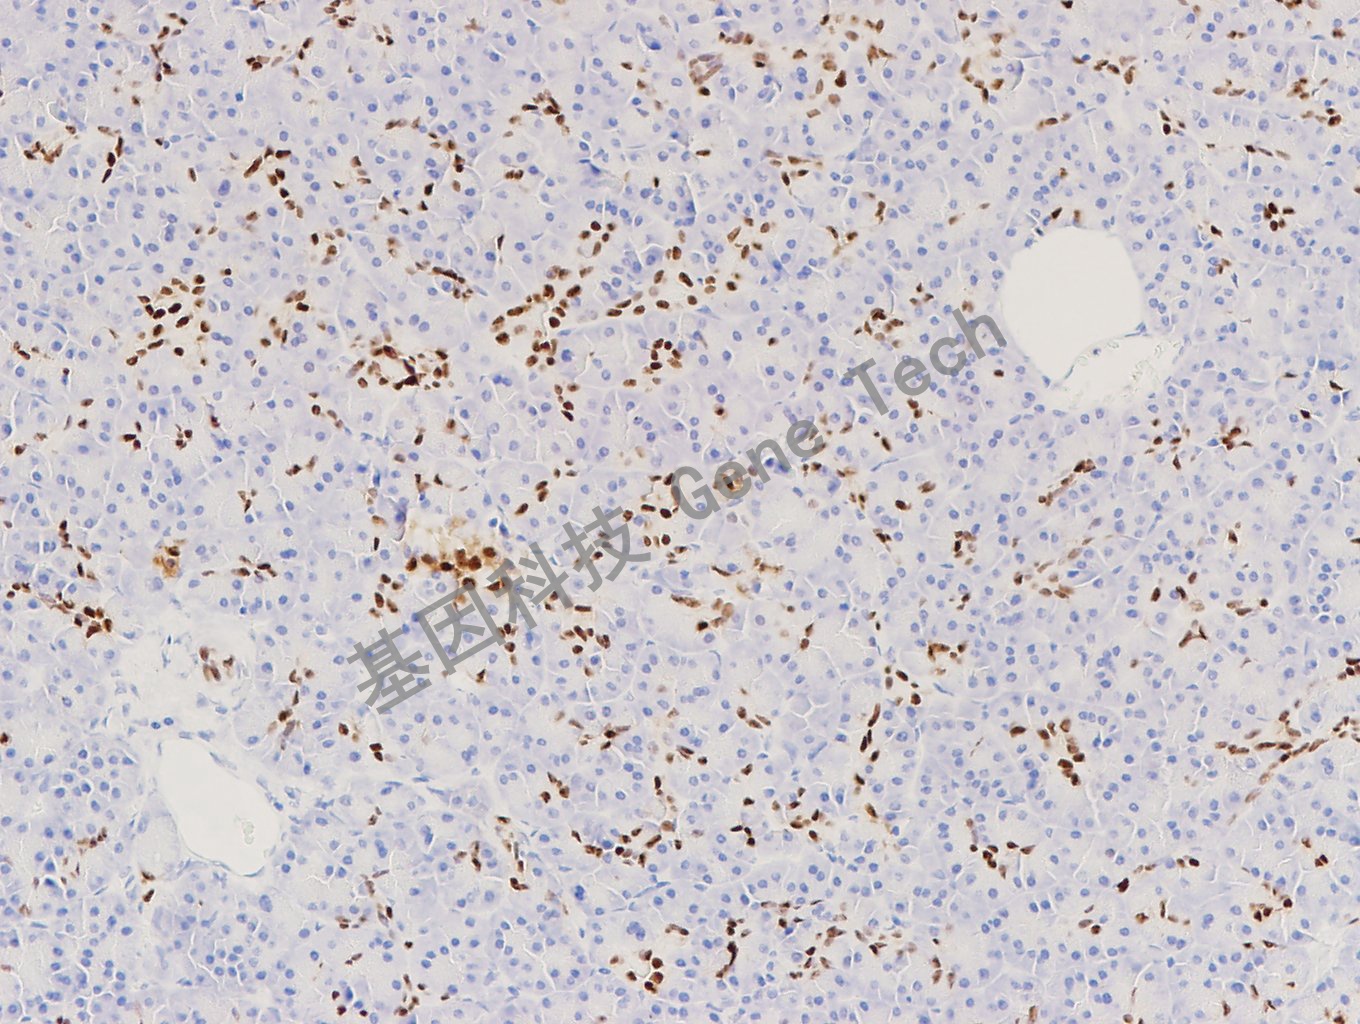

胰腺石蜡切片,用 PDX1(GT2293)染色,细胞核阳性,DAB 显色。